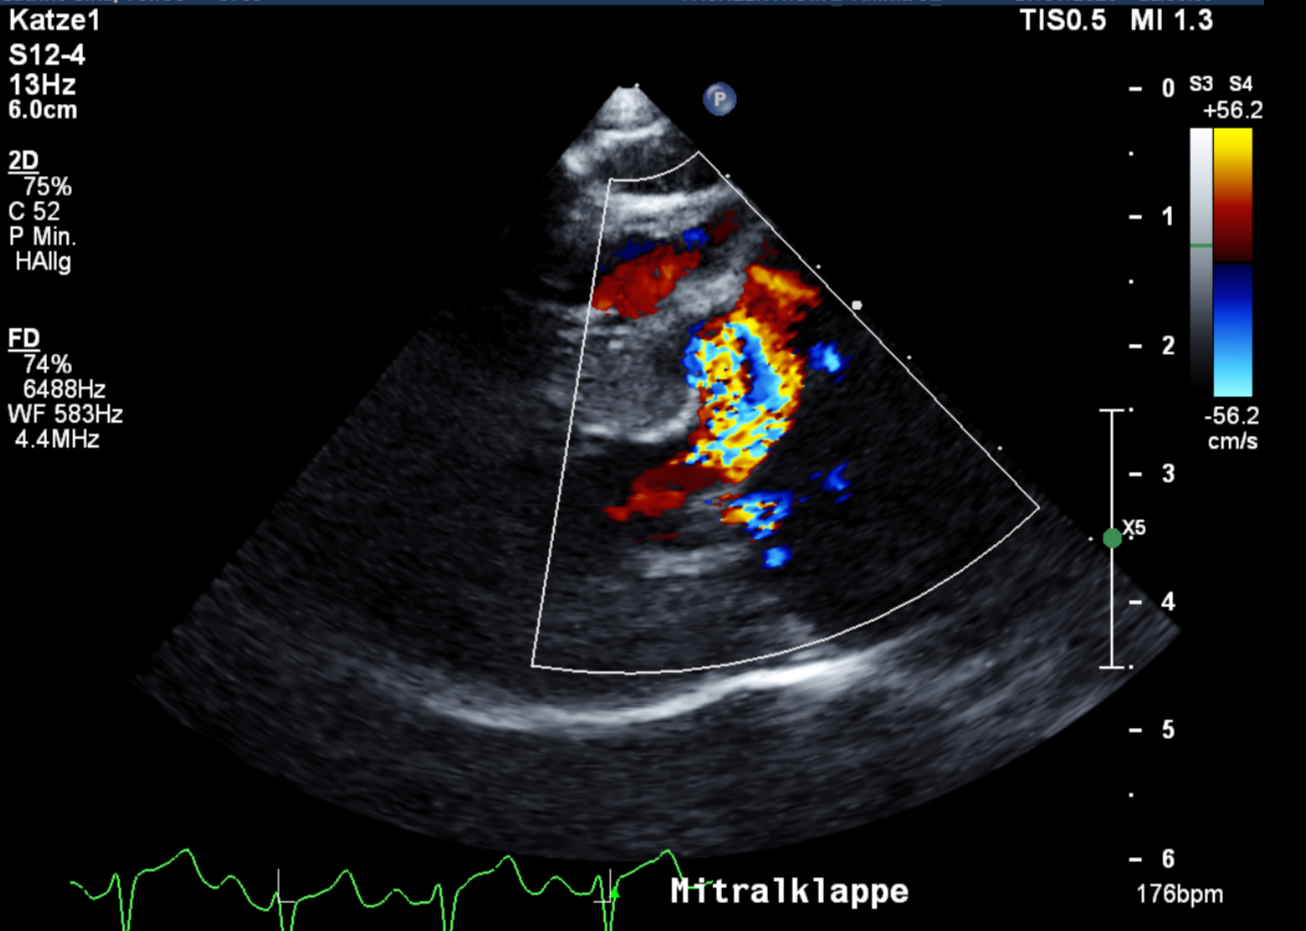

Ab einem gewissen Alter sollte daher ein regelmäßiger Check-up des Herzens obligatorisch sein. Neben dem Doppler- und B-Mode- Herzultraschall, gehören das EKG, das Röntgen zum manchmal auch Blutuntersuchungen zur vollständigen Abklärung der Herzgesundheit dazu. Frau Dr. Theresa Eulitz (Zusatzbezeichnung Kardiologie) ist unsere Spezialistin in Herzensangelegenheiten.